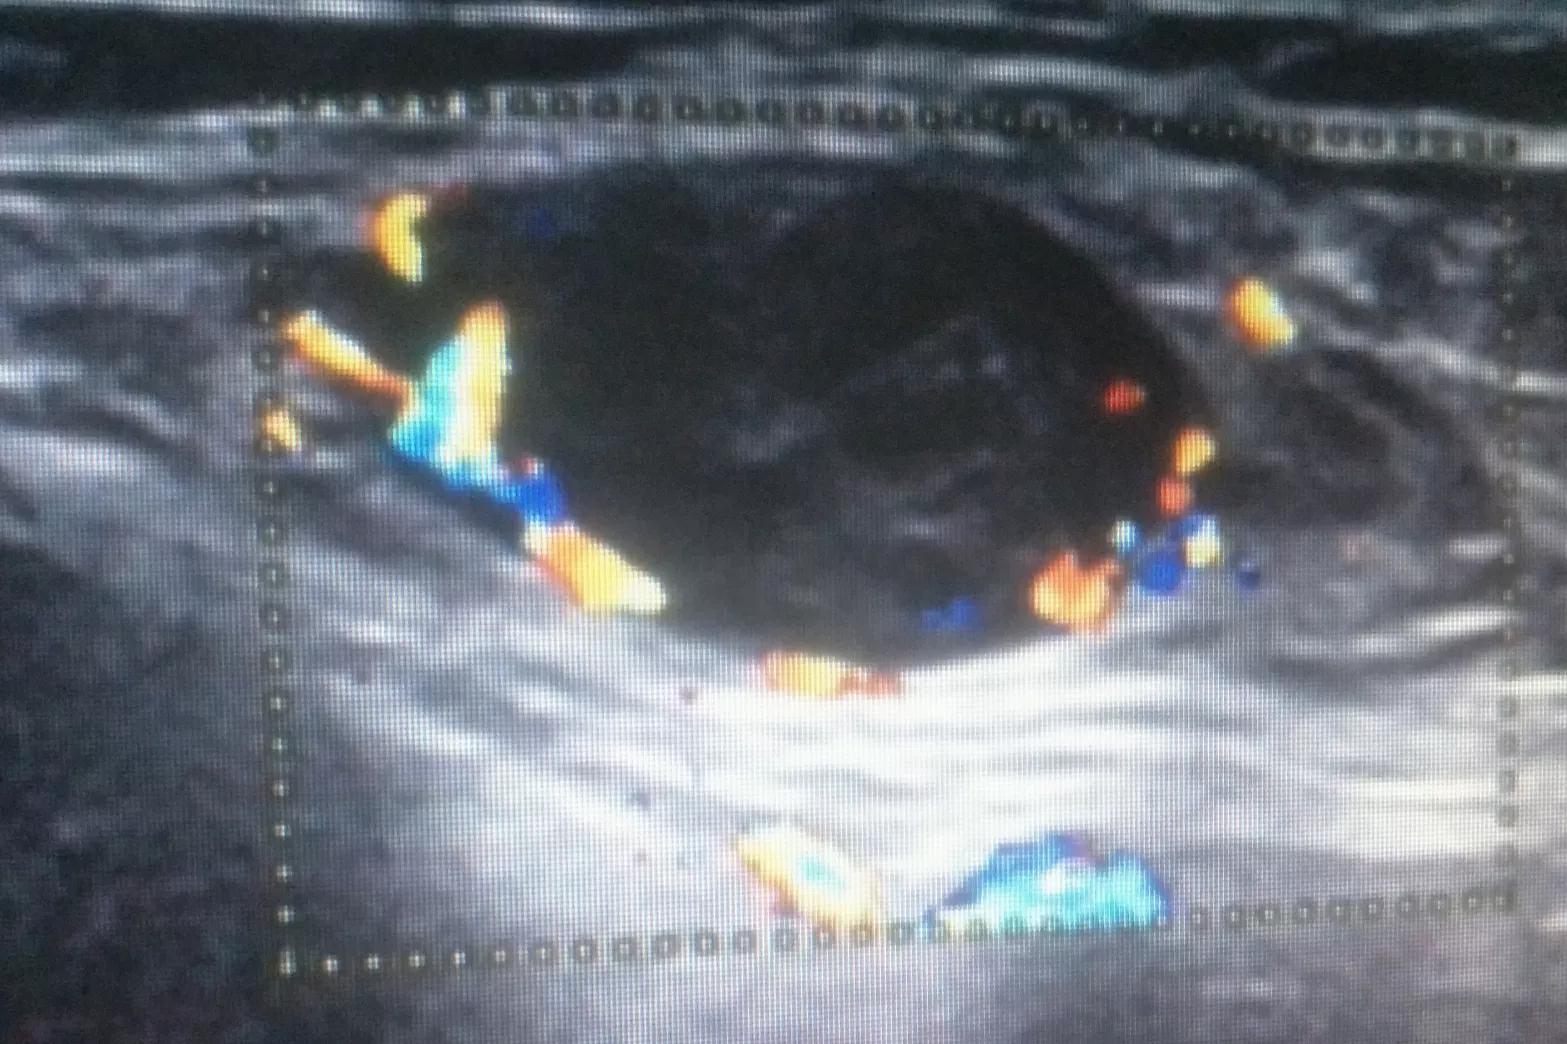

这天,小郑突然在左下腹似乎触到一个包块。她赶紧跑到超声科做一个检查,超声所见左附件区探及一大小约12x8cm混合性包块,包块内见血流信号。这是一种原发性胃癌转移到卵巢形成的肿瘤,是一种特殊的转移性腺癌,叫库肯勃瘤,又叫印戒细胞癌?

肿大淋巴结的超声图像,血运非常丰富。